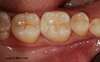

Avant

Molaire cariée

Dent avant pose onlay